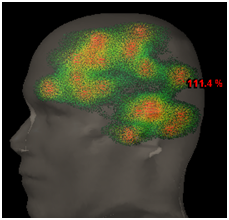

A 63-year-old woman with a history of breast cancer of 5years of evolution with bones metastasis controlled with systemic treatment and 2years later presented cerebral metastases treated with WBRT sparing both hippocampus (20Gy in 5 fractions). One year at the end she has new brain progression without neurological symptoms and controlled systemic disease. We evaluated the case and in view of the good general condition we indicated re-irradiation with radiosurgery to all visible lesions: 83 (eighty-three) in total (Figure 1). The total volume of disease was 34cc and the dose prescription of SRS 27Gy in 3 fractions. For the treatment, we used a dedicated linear accelerator (LINAC) Trilogy Varian, frame less immobilization and RapidArc modulated intensity radiotherapy technique (IMRT) with an treatment isocenter. After 6months of follow-up, there was no neurocognitive impairment or alteration of quality of life, without systemic progression and in the brain resonance complete response was seen in 90% of the lesions with tumor control of all the metastases (Figure 2).

Figure 1 83 metastases, 3D reconstruction.